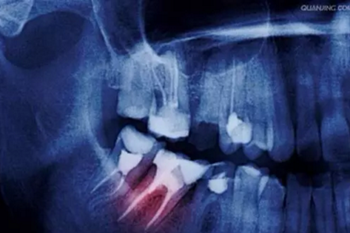

5、不愿意拍牙片

一些人不愿意照牙片,認(rèn)為醫(yī)生看看牙齒情況就可以了。

要知道醫(yī)生的眼睛不是透視鏡,牙齒好比大樹,樹根扎在土壤里,而我們的牙根也埋在牙槽骨里,牙根的狀態(tài)、里面的神經(jīng)肉眼都是看不到的。

只有通過牙片,牙醫(yī)才可以確切了解齲壞的范圍、牙痛是由牙髓炎還是根尖炎或是牙周炎引起、種植牙需要的骨量等等。

牙疼才去看牙?牙科最良心科普都在這里了!

圖:種植牙牙片

牙片為醫(yī)患溝通提供了準(zhǔn)確的依據(jù)。

有些家長還認(rèn)為孩子拍牙片會(huì)受到輻射,對(duì)身體不好,其實(shí)大可不必?fù)?dān)心,牙科X光片對(duì)身體輻射量相當(dāng)?shù)停⑶艺?guī)牙科都會(huì)配備防輻射服,影響微不足道。

建議

相信醫(yī)生,拍牙片只能對(duì)你有好處,也可以為你保留最原始資料,更可以讓醫(yī)生準(zhǔn)確判斷你的病情,更好地為你治療。